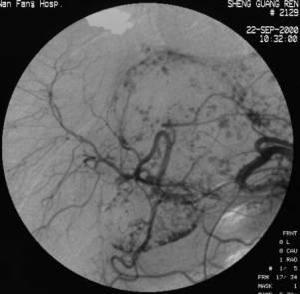

4.腹腔血管造影 先行腹腔動脈和腸系膜上動脈造影,確定動脈期造影劑無血管外漏,在靜脈期看見胃十二指腸靜脈、胰十二指腸靜脈增粗、蛇行或結節狀曲張及造影劑流向下腔靜脈可以確診。在出血明顯時可見到造影劑漏出血管外。高度懷疑本病時經皮經肝門靜脈造影也有價值。進行經胃結腸支的造影可得到有關門靜脈的非常鮮明的影像。經通常的腹腔動脈和腸系膜上動脈造影容易獲得病因血管影像,而且檢查後還可繼續進行栓塞術。